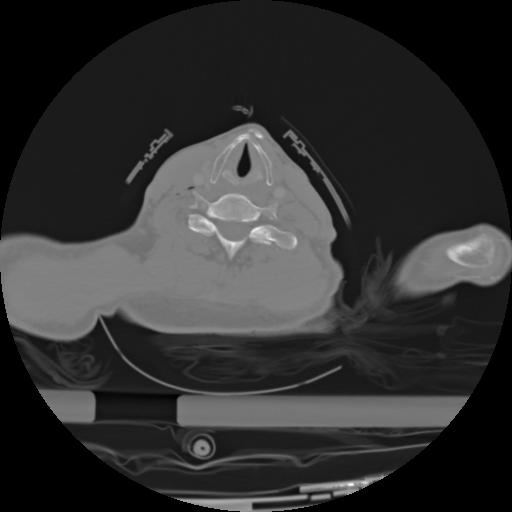

21 ANGIO,CE,Axial,3.0,ANGIO,,